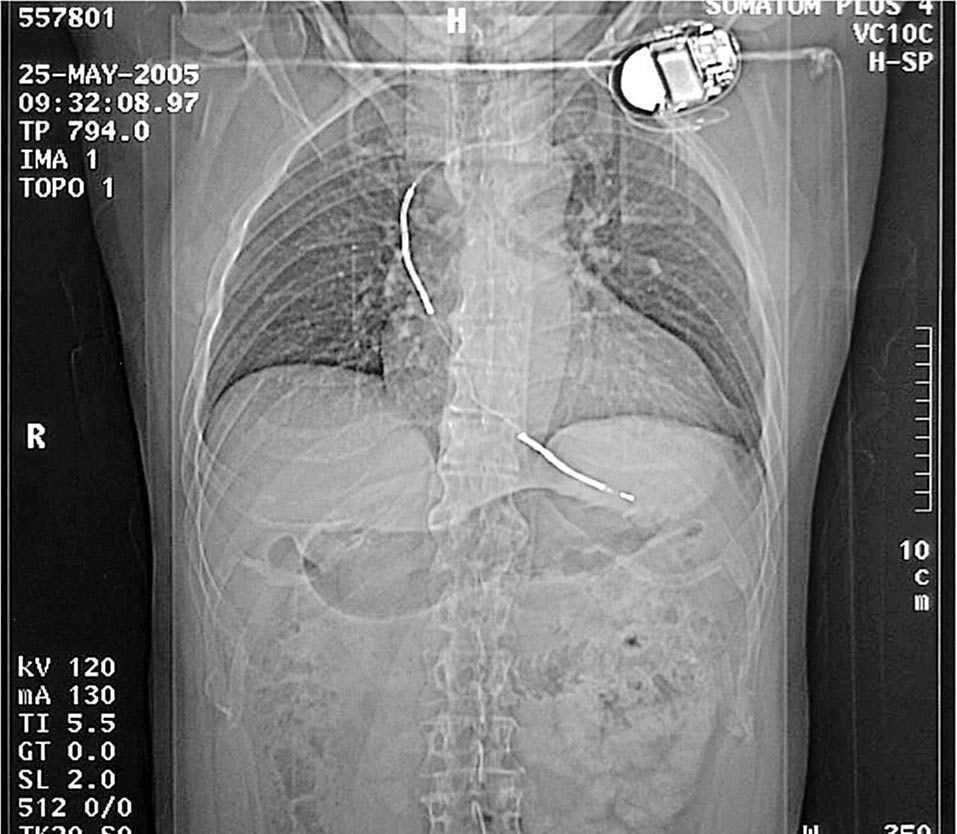

Varón, sin antecedentes dignos de interés, con historia de infarto de miocardio 8 años antes y dispositivo marcapasos desfibrilador implantado (fig. 1). Presenta dolor abdominal brusco (hipocondrio izquierdo) que irradia al hombro del mismo lado, así como malestar general. El ECG fue demostrativo de infarto anterior previo. Los estudios analíticos se encontraban dentro de la normalidad. La tomografía computarizada mostró un aneurisma ventricular con trombos murales claramente manifiestos (fig. 2) y un infarto esplénico segmentario. Se estableció anticoagulación con heparina fragmentada subcutánea y después se mantuvo con dicumarínicos. Pasados 3 años, el paciente se encuentra en buen estado general y no ha tenido ningún tipo de complicación evolutiva en el bazo y continua con su tratamiento anticoagulante.

Fig.1.Radiografía torácica.Paciente con desfibrilador automático.